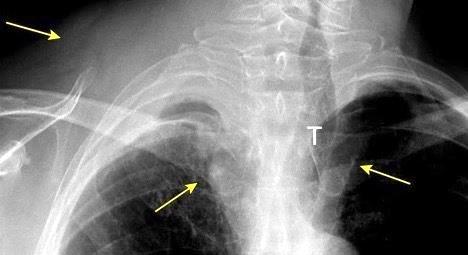

Carcinoma subglótico

Tumor poco frecuente. 1,8% de los tumores laríngeos.

Tendencia a invadir el anillo cricoideo y el esófago.

Ganglios + frecuentes

Mac Neill SD et al. Survival of patients with subglottic squamous cell carcinoma. Curr Oncol. 2018